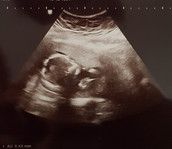

Schwanger oder Zyste???!

kurz zu mir. Ich bin 27 Jahre alt und wünsche mir seit ca. 2 Jahren ein Kind. Wir haben uns aber nicht darauf versteift und hatten GV wenn wir Lust hatten und nicht nach "Termin". Ich habe vor ca. 3 Jahren die Pille abgesetzt und wir verhüten nicht. Bis jetzt ist auch noch nichts passiert aber aktuell ist etwas anders..

Gott sei Dank hab ich morgen gleich den Termin - mach mir jetzt aber natürlich Gedanken ob das nicht ne Schwangerschaft ist sondern eher eine Zyste oder schlimmeres.. Das verdammte Googel - man macht sich selber so verrückt.. aber was meint ihr? Könnte eine Schwangerschaft möglich sein?

Danke schon mal für eure Meinung. Wenn ich schwanger wäre wäre ich Freitag in der 4 SSW..